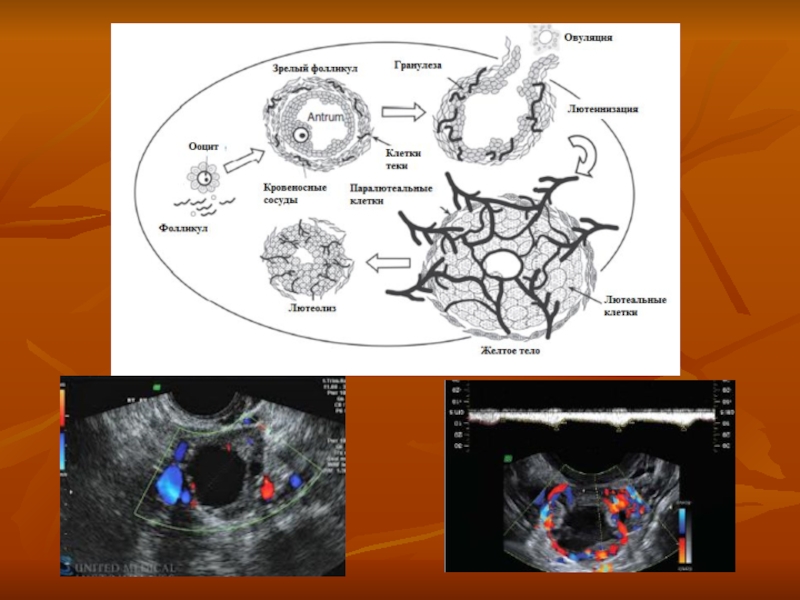

Слайд 323 физиологических процесса составляющих овуляцию

Переход от продукции эстрадиола к продукции прогестерона

и эстрадиола

Возобновление мейоза

Выход комплекса ооцит-кумулюс за пределы фолликула